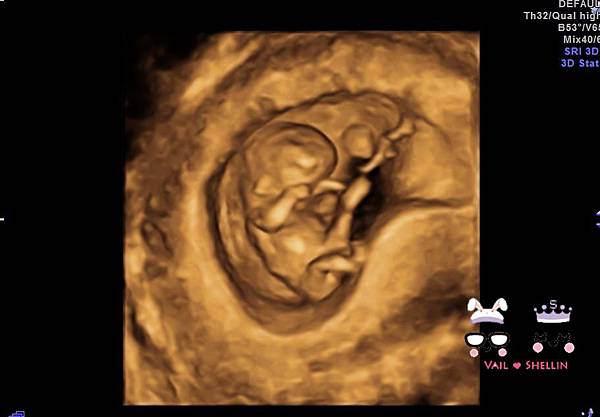

醫生還讓我們看了4D的照片~

4D更像是一個人啦~~

寶寶看起來很像在揉眼睛@@

是說不知道是不是在睡覺~

我都沒有看到他在動~XDD

這照片就不太需要發揮想像力了